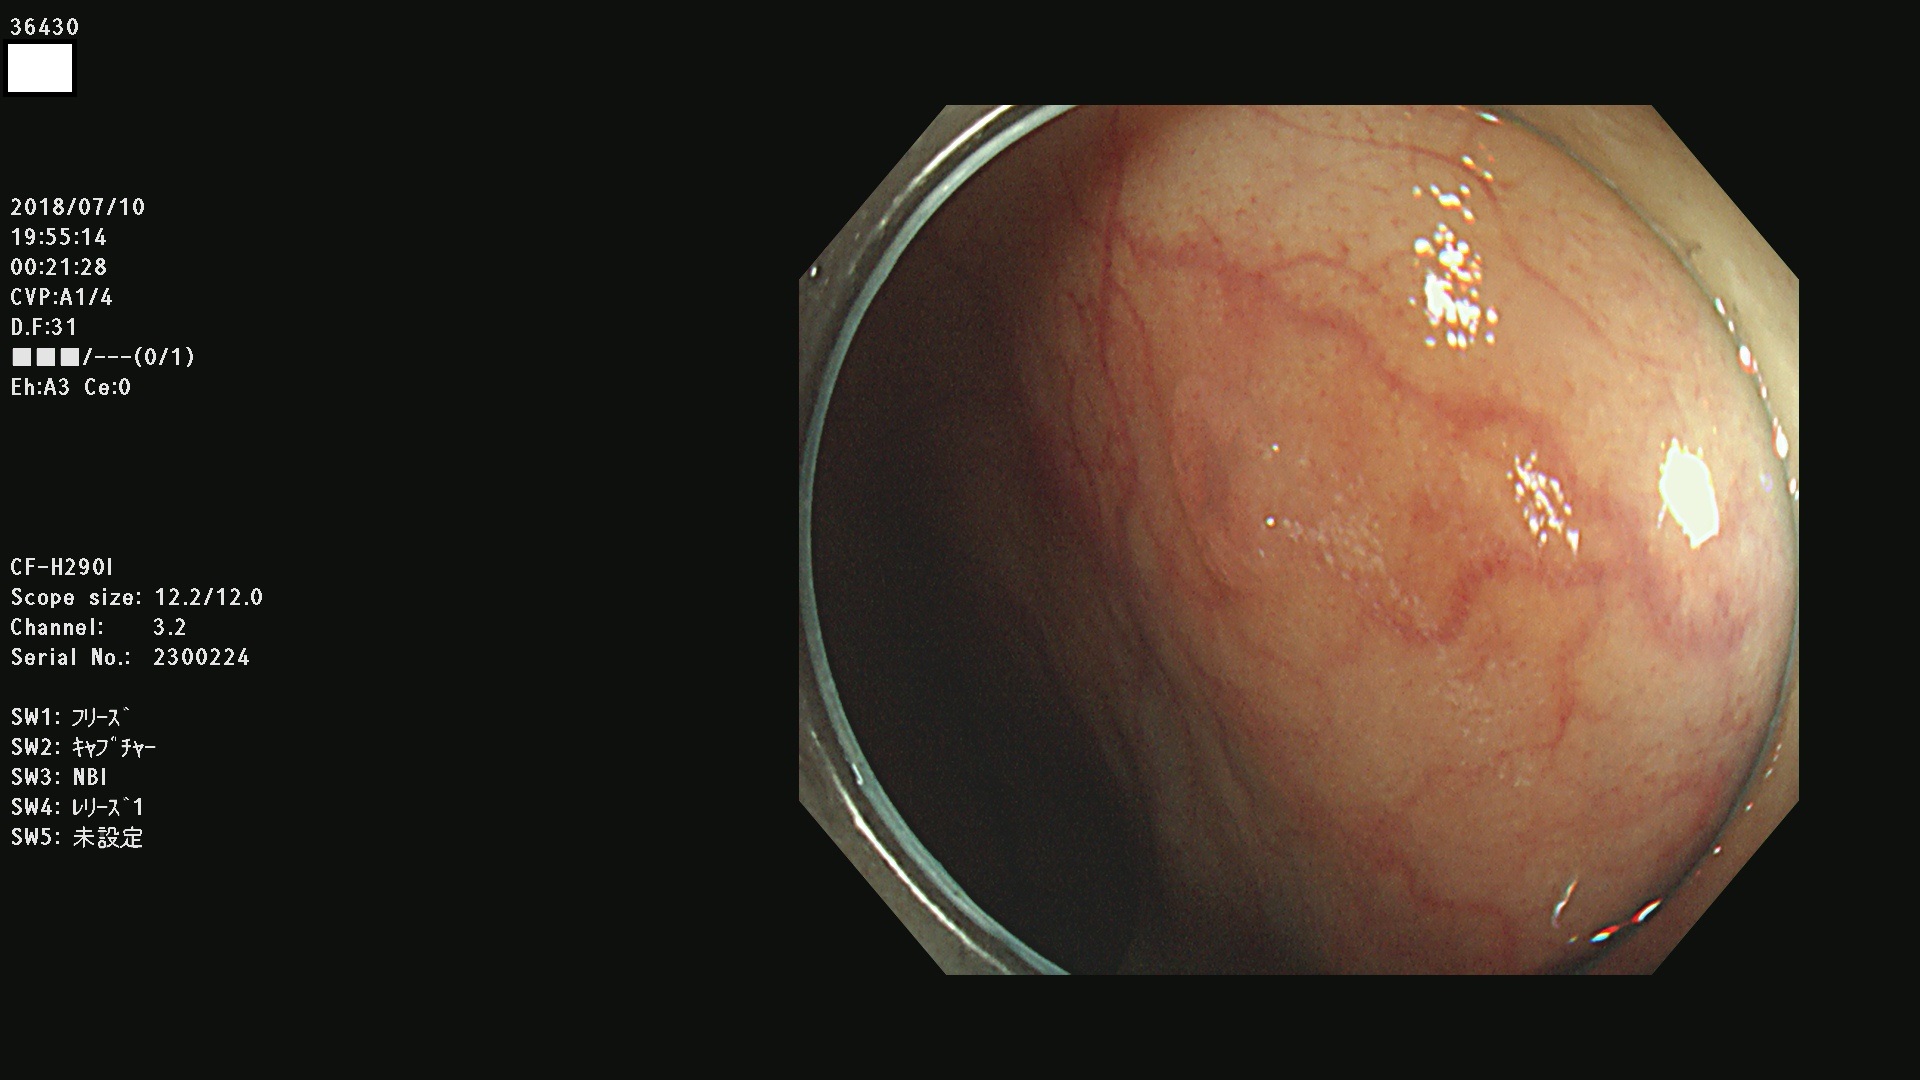

36400(SSAPのみ) 36402 36403 36404 36405 36406 36407 36408(SSAPのみ) 36412 36413 36414 36415 36416 36417 36418 36420 36422 36423 36424 36425 36426 36428 36429 36430 36431 36434 36435 36436 36437 36438 36440 36443 36447 36448 36449 36450 36452 36454 36458 36459 36460 36462(SSAPのみ) 36463 36464 36465 36466 36470 36471 36472 36473 36474 36475 36476 36478 36480 36481 36482 36484 36487 36488 36489 36490 36492 36494 36495 36496 36497 36498